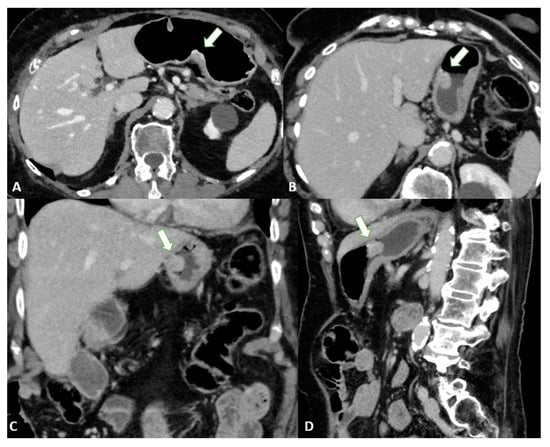

To distinguish normal from pathologic nodes, size is the most accepted parameter. However, there is no clear consensus on the threshold size for suspicious nodes. The threshold size depends on the location and ranges from 6 to 10 mm in the upper abdomen [34]. Other characteristics of metastatic nodes include a round shape, a cluster of more than three nodules, and the degree and heterogeneity of enhancement [35] (Figure 8).

Figure 8.

Axial 2D images in the portal venous phase show different pathological node locations (black asterisks): (A) pathological lymph nodes in the lesser curvature of the stomach; (B) pathological lymph nodes of the lesser curvature and the celiac artery; (C) pathological lymph nodes of the pancreatic head and para-aortic region. The lymph nodes in the images present an inhomogeneous contrast enhancement with central hypodensity due to the presence of necrotic components inside.

In addition, microscopic metastases can often be found in normal-sized nodes in patients with EGC, which reduces the accuracy of N staging in EGC compared with advanced cases [24].

According to a meta-analysis [10], the CT sensitivity and specificity of N staging range from 62.5 to 91.9% and 50.0 to 87.9%, respectively. These diagnostic values are associated with an acceptable accuracy level (86.3%), but the authors [36] highlighted an important problem with N-staging based on the mediocre to good inter-reader reliability (κ 0.449–0.662) in classifying the nodal status.

Nodal staging with MPR showed no significant improvement [23], with overall accuracy levels of 62% and 64% for axial images and MPR, respectively.